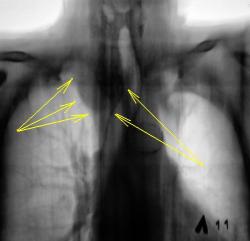

Синяя стрелка, как понимаю "кругляк", который смущает Валентина Львовича? К сожалению край изображения, тяжело что-то понять. Вероятнее всего это 1 ребро.

Зато Красная стрелка - явно зоб

При "клике" на то, что помечено красной стрелкой, дифференцируются известковые включения?